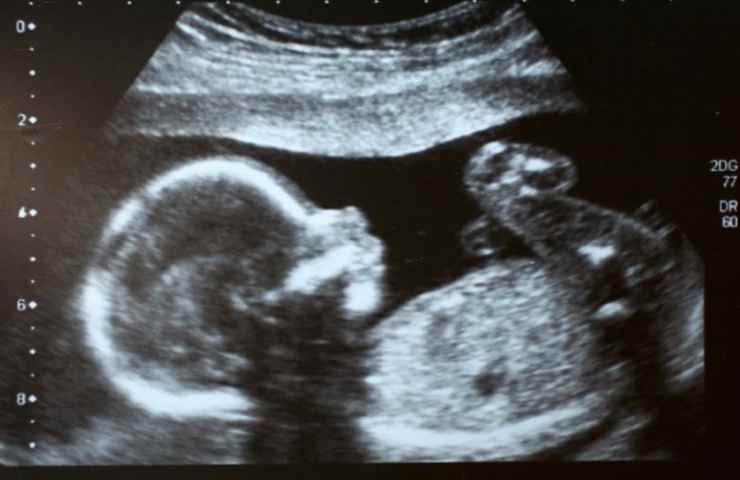

Il Bi-test si concentra sull’analisi di due specifiche proteine placentari nel sangue materno: la free beta Hcg e la PAPP-A. Questi indicatori, insieme alla misurazione della translucenza nucale tramite ecografia, offrono stime significative sulle probabilità che il nascituro possa essere affetto da condizioni come la sindrome di Down, Trisomia 13 o 18, Sindrome di Turner o Sindrome di Klinefelter.

È cruciale comprendere che il Bi-test non funge da esame diagnostico definitivo ma piuttosto come un filtro iniziale. Serve a identificare le donne che potrebbero avere un rischio elevato di portare avanti una gravidanza con potenziali anomalie cromosomiche. In presenza di risultati anomali, si rendono necessari esami più specifici e invasivi, come l’amniocentesi o la villocentesi, per conferme diagnostiche.